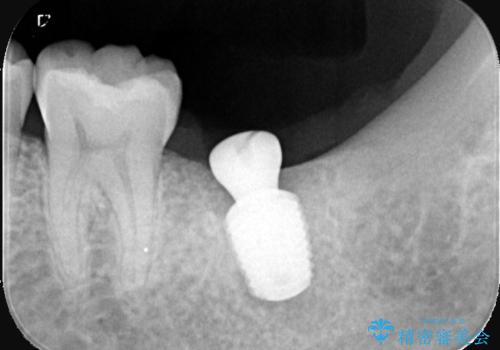

- 「歯茎の腫れ」を主訴に来院された患者様です。検査の結果、エンドペリオ病変と診断いたしました。

治療方針としては、保存的治療と抜歯後のインプラント治療の2つの選択肢をご提案させていただきました。

患者様ご自身が抜歯後のインプラント治療をご希望されたため、インプラントによる治療を行いました。